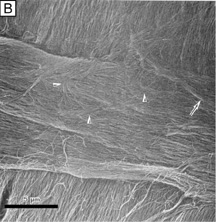

A number of factors have been known to acutely affect the barrier function of the endothelium, including the following: reversible disruption of cell junctions (calcium-free solutions or glutathione-restricted solutions [Fig. 25]), mechanical damage (e.g., trauma, intraocular lens [IOL] insertion, surgical instruments), or chemical injury (e.g., noncomplete toxic intraocular solutions, preservatives). Fortunately, if enough of the remaining viable cells are able to migrate, recover the posterior corneal surface by spreading out over a larger surface area, and reestablish the intercellular cell junctions, the barrier function of the corneal endothelium is restored.

Fig. 25. Scanning electron micrograph (1,000×) of the endothelium after perfusion with calcium free irrigating solutions after 30 minutes. Without calcium, endothelial cells round up into small mounds as the intercellular junctions become disrupted, resulting in exposure of large areas of Descemet's membrane, loss of barrier function, and corneal swelling. E, endothelial cells; ES, extracellular space. Bar = 10 μm.